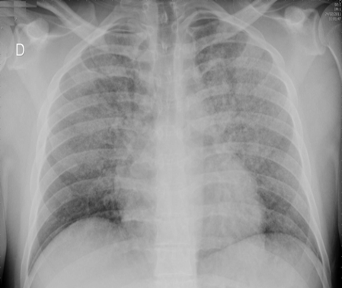

Rx toracică, incidență P-A

DESCRIERE:

pe tot teritoriul pulmonar, bilateral → opacități nodulare multiple de dimensiuni variabile, intensitate medie-mare, omogene, cu contur imprecis delim

confluente

distribuție anarhică

DX: bronhopneumonie

DD:

miliara TBC

MTS pulm hematogene